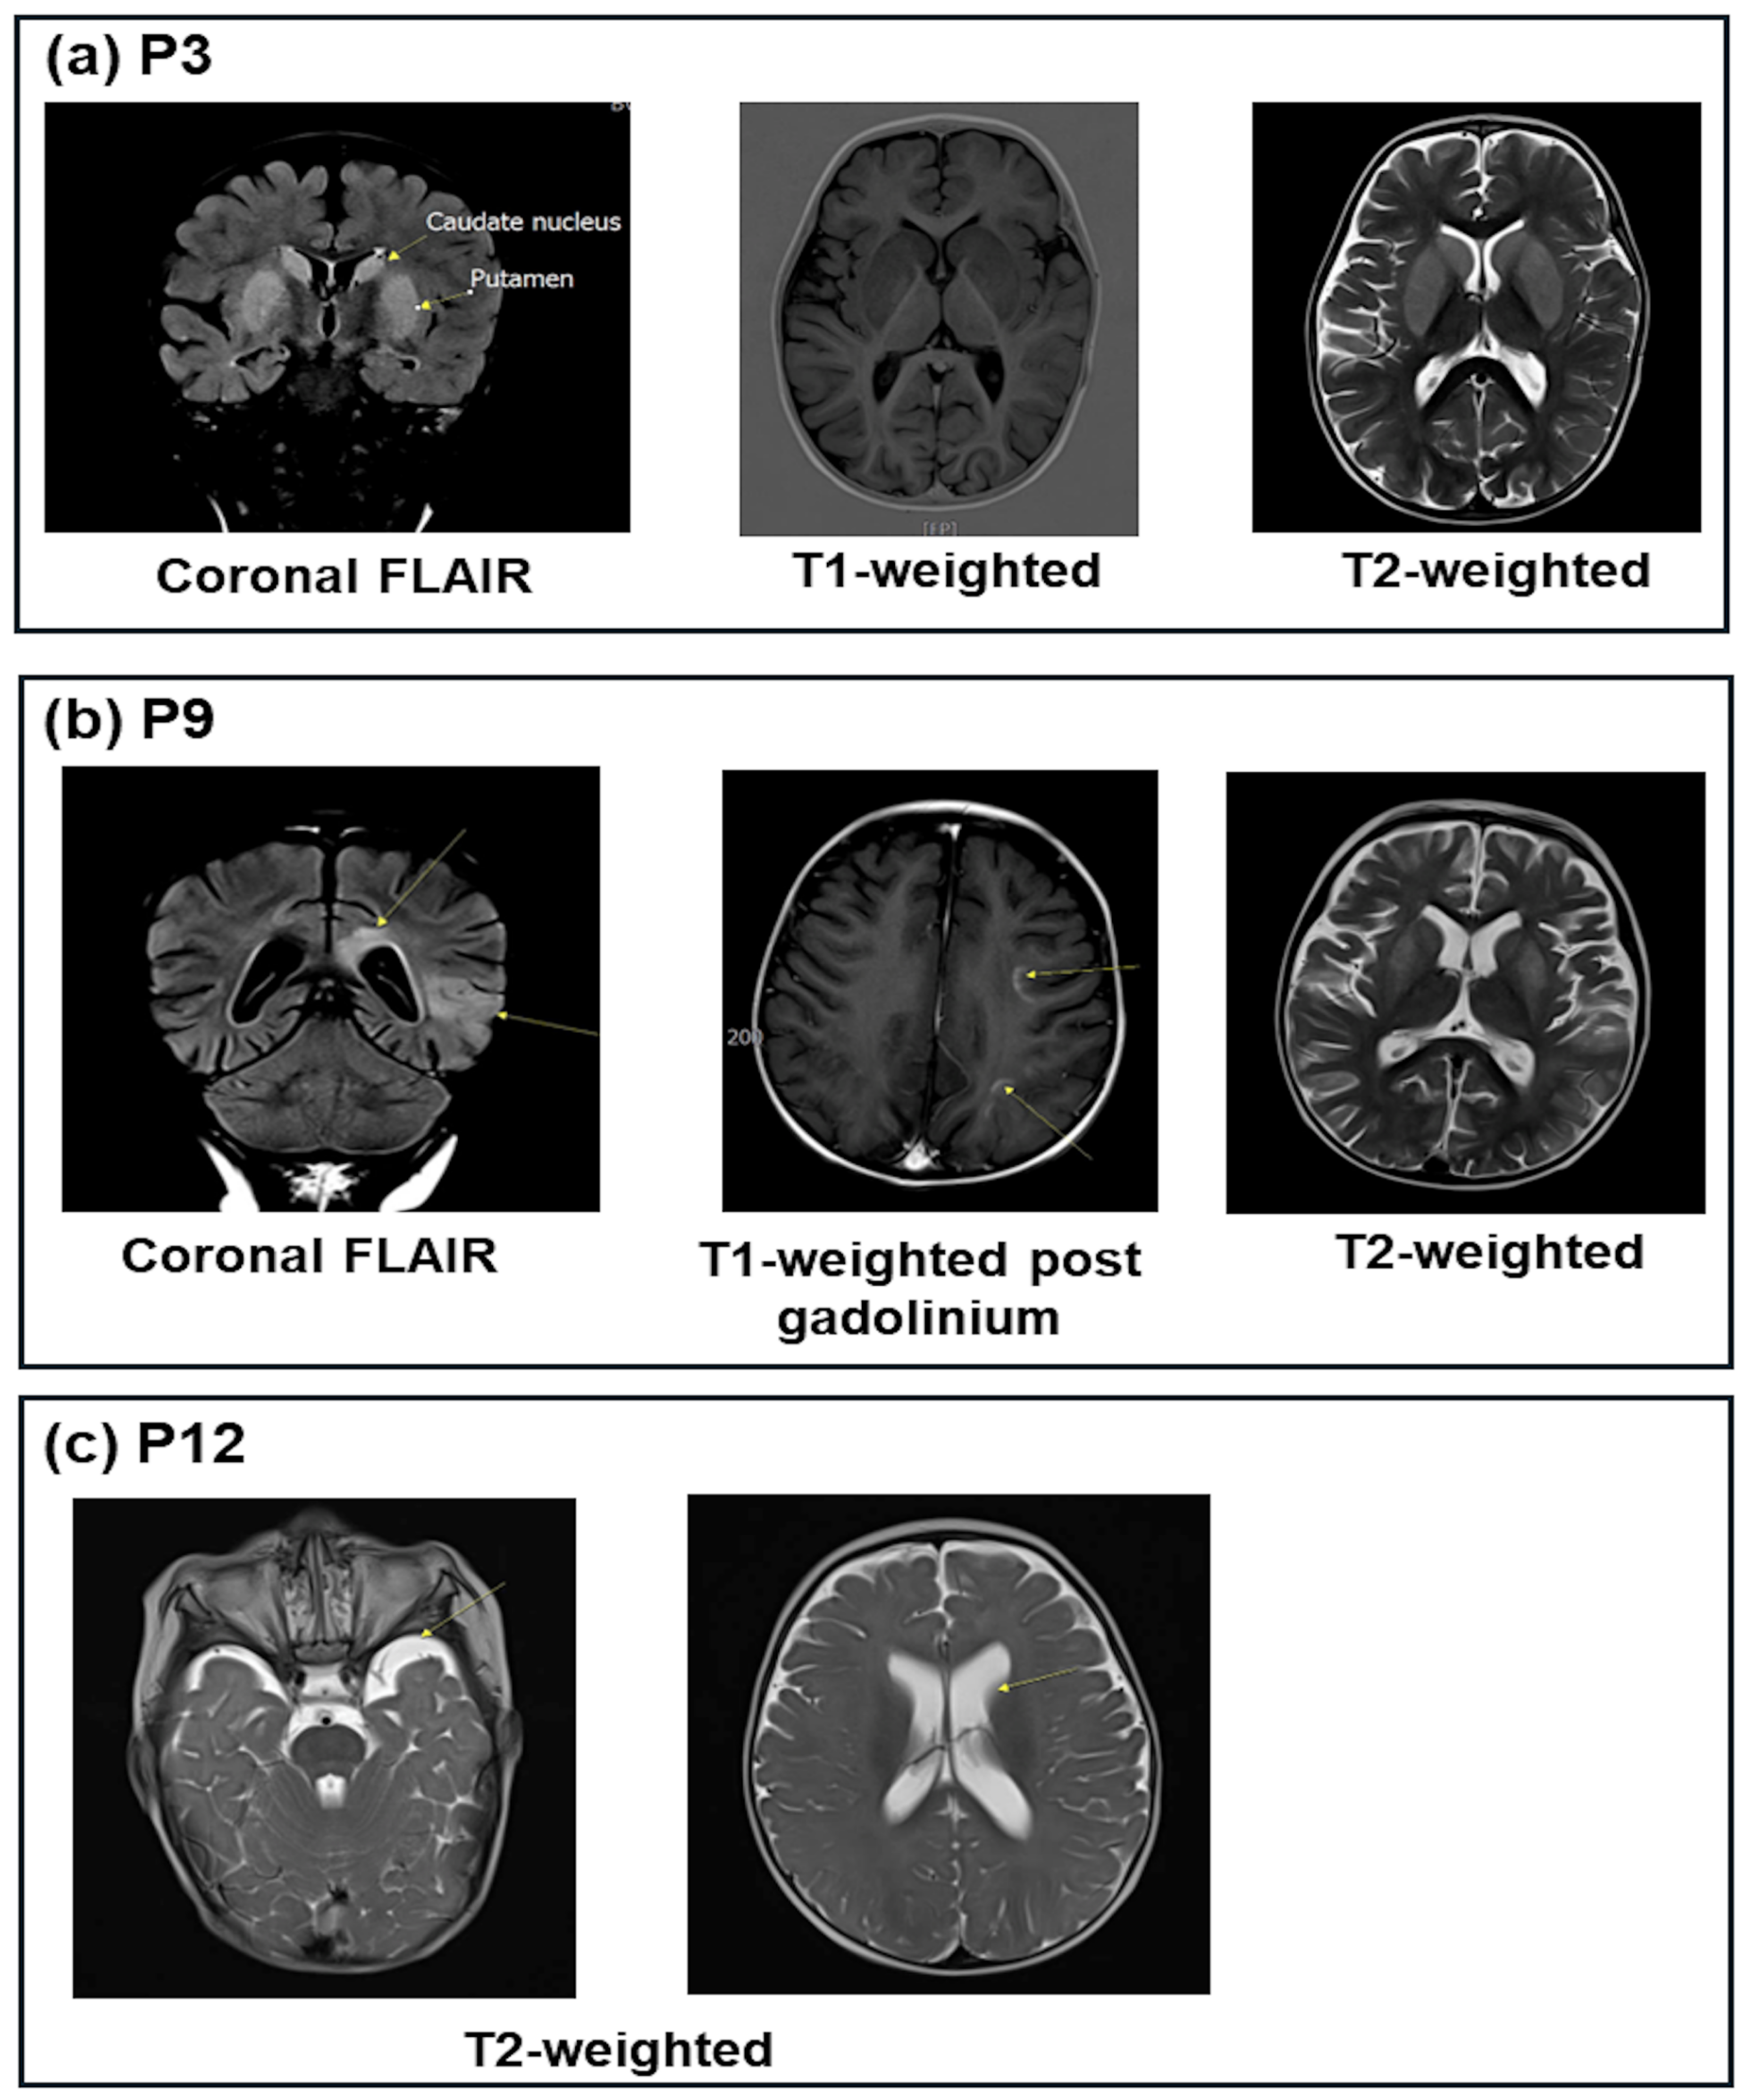

| P3 | ↓0.8 | 7.12 | 9.6 | −21.0 | 51.6 | ↑108 | ↑209 | ↑2287 | ↓4.4 | 27.0 | - | 1+ | Lesions of the bilateral putamen caudate |

| P9 | 3.82 | 7.00 | 8.6 | −20.0 | 49.2 | ↑126 | ↑143 | NA | 16.7 | 8.8 | - | Neg | Bilateral cerebrum lesions |

| P12 | ↓2.48 | 7.37 | 7.5 | −15.6 | 36.4 | ↑132 | ↑270 | NA | ↓3.8 | 19.7 | - | 1+ | Slight ventilation dilation |